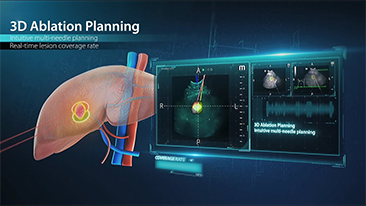

Aparaty ultrasonograficzne z serii Resona, dzi?ki szerokiej gamie za pomoc? wszechstronnych sond do r√≥?nych zastosowaŇĄ i wydajnych narz?dzi do zastosowaŇĄ klinicznych, pomagaj? U?ytkownikom stawia? dok?adniejsz? i efektywniejsz? diagnoz? oraz ocenia? wyniki.